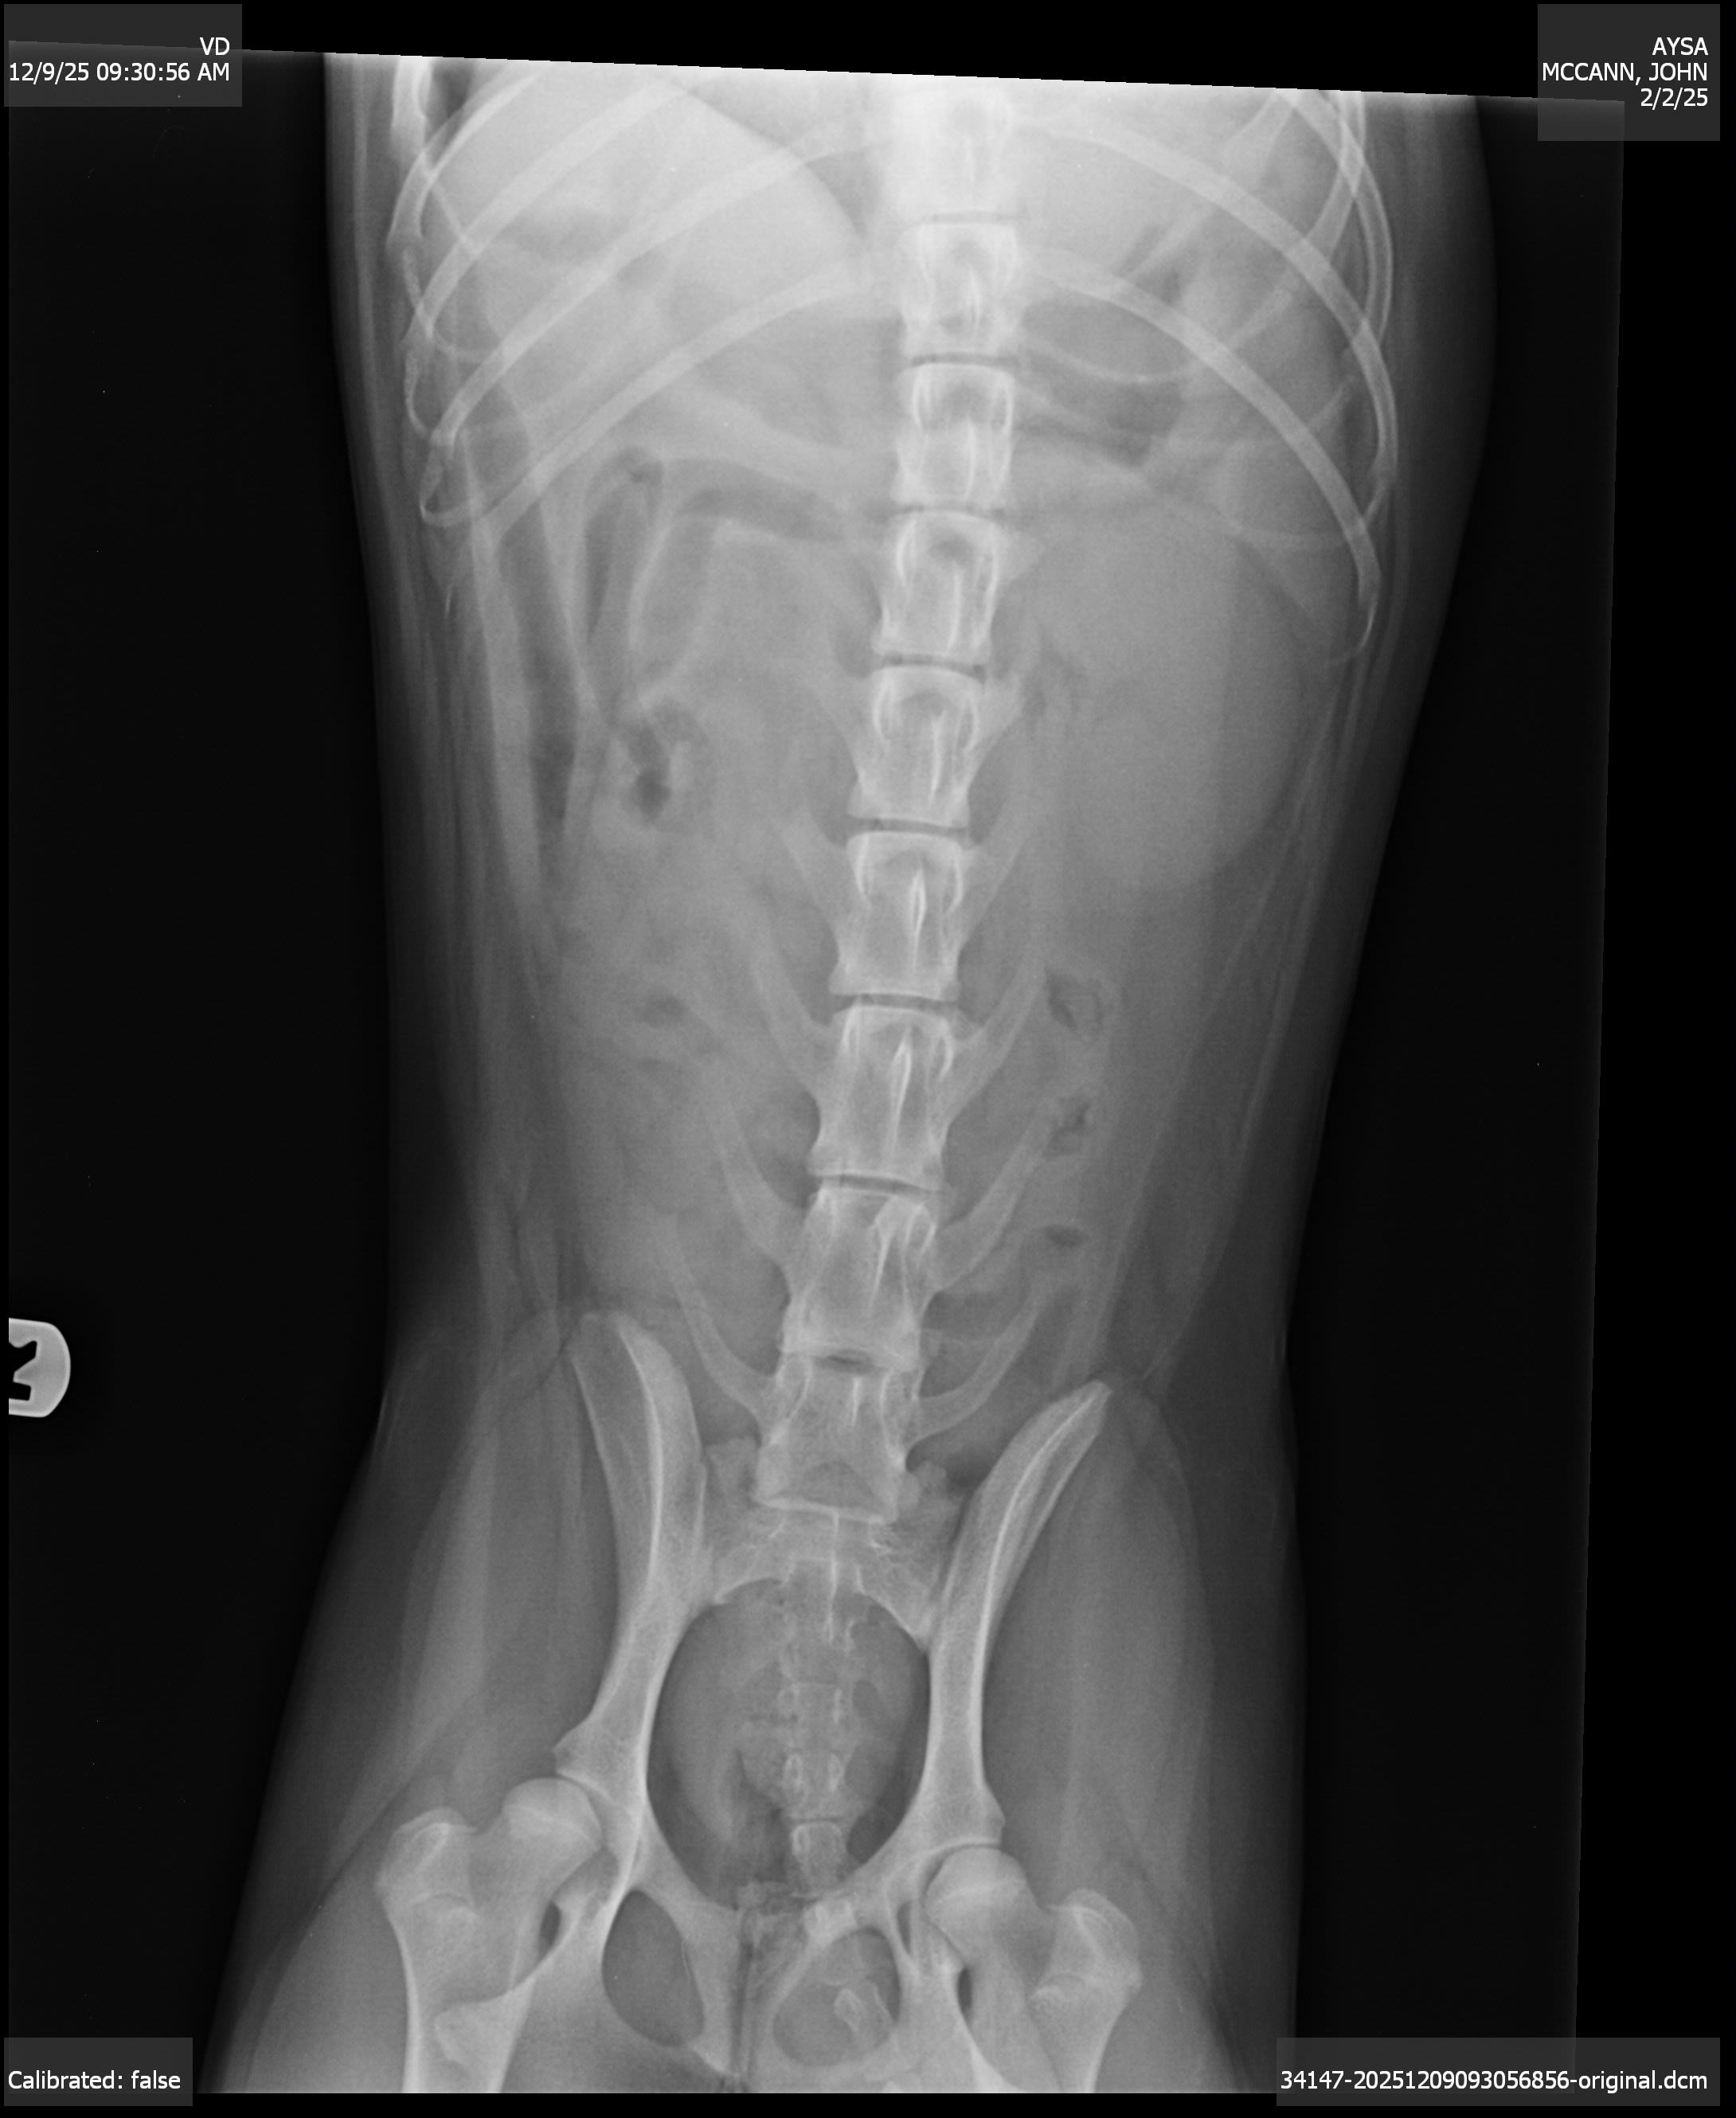

She finally got into the vet and went into emergency surgery around 2 PM today. The vet originally thought she had swallowed a toy, but once they opened her up, they discovered something much worse, severe chronic stomach ulcers and extremely thickened, inflamed stomach tissue that looked like a mass. These ulcers were bleeding into her stomach and causing her to vomit blood. Her gums were pale, and she could barely stand without help.

During surgery, she also began bleeding from her nose. The vet is now concerned she developed aspiration pneumonia from all the nonstop vomiting. Because of everything going on, Aysa has to stay in the hospital for at least two nights on IV fluids and medications. She’s far too sick to come home right now.